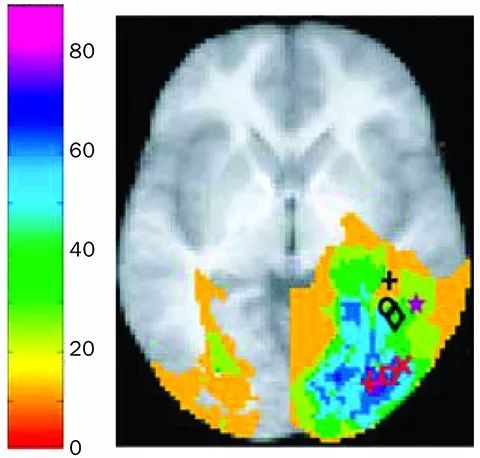

大脑中很多个部位都参与了对容貌影像的信息处理,不过影像学研究表明一个叫做梭状回面孔区(fusiform face area,FFA)的部位尤其重要,这是大脑颞叶的一部分,颞叶则是耳朵上方的一大块大脑皮层。大脑后部的枕叶面部区(occipital face area)可能也扮演着重要角色,负责分辨看到的物体是不是人脸。同样在颞叶里的颞叶上沟(superior temporal sulcus)能够对被观察者的表情变化和视觉角度变化作出反应。

美国加利福尼亚大学洛杉矶分校的研究人员发现,大脑中参与面孔识别的部位有些分散。他们观察了因脑损伤或脑疾病而患有面容失认症、无法记住他人长相的病人的脑损伤部位。多数病人是图中紫色和深蓝色的部位受损,其次是浅蓝、绿色和黄色的部位。病人受损最多的部位在面孔识别中具有最重要的作用。其中一些部位与影像学实验中受试者处理面部图像时最活跃的部位吻合,这些活跃的部位包括梭状回面孔区(黑色),枕叶面部区(红色)和颞叶上沟区(紫色)。